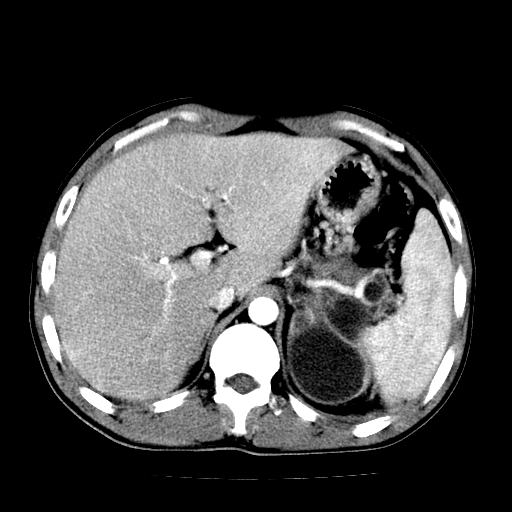

以下是引用天南地北在2007-4-30 13:36:00的发言:[br]支持慢性胰腺炎伴有假性囊肿

以下是引用andymaomao在2007-4-30 14:28:00的发言:[br]支持:1.慢性胰腺炎并假性囊肿形成可能;[br] 2.左肾形态稍增大,旋转不良。